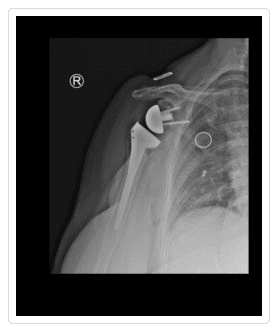

Similar to the standard total shoulder replacement procedure, the reverse operation involves replacing the ball of the joint and the socket with artificial components. However, the placement is reversed. The plastic socket is placed at the top of the upper arm bone (humerus) and the metal ball is attached to the shoulder blade (scapula). This technique was designed for patients with painful arthritis who do not have a functional rotator cuff. A standard shoulder replacement essentially resurfaces the bone surfaces and depends on the rotator cuff to function properly. Without the rotator cuff, standard replacement surgery has an unacceptably high risk of early failure.

The rotator cuff plays a highly important role in lifting and rotating the shoulder. As such, when it is damaged, the shoulder can become immobile. Designed in the 1970s and refined in the last 10-15 years, the reverse shoulder replacement allows the deltoid muscle on the outer shoulder to lift and rotate the arm, substituting for the rotator cuff. While not as predictable as the standard replacement, the reverse prosthesis is often the only option for severe pain and weakness from rotator cuff arthropathy (arthritis with torn rotator cuff), certain fractures and revision surgery for failed prostheses.